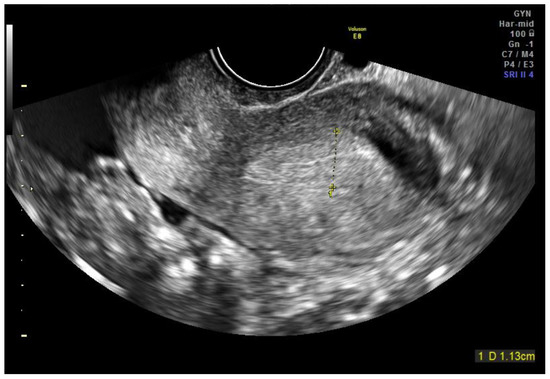

2.1. Case Report